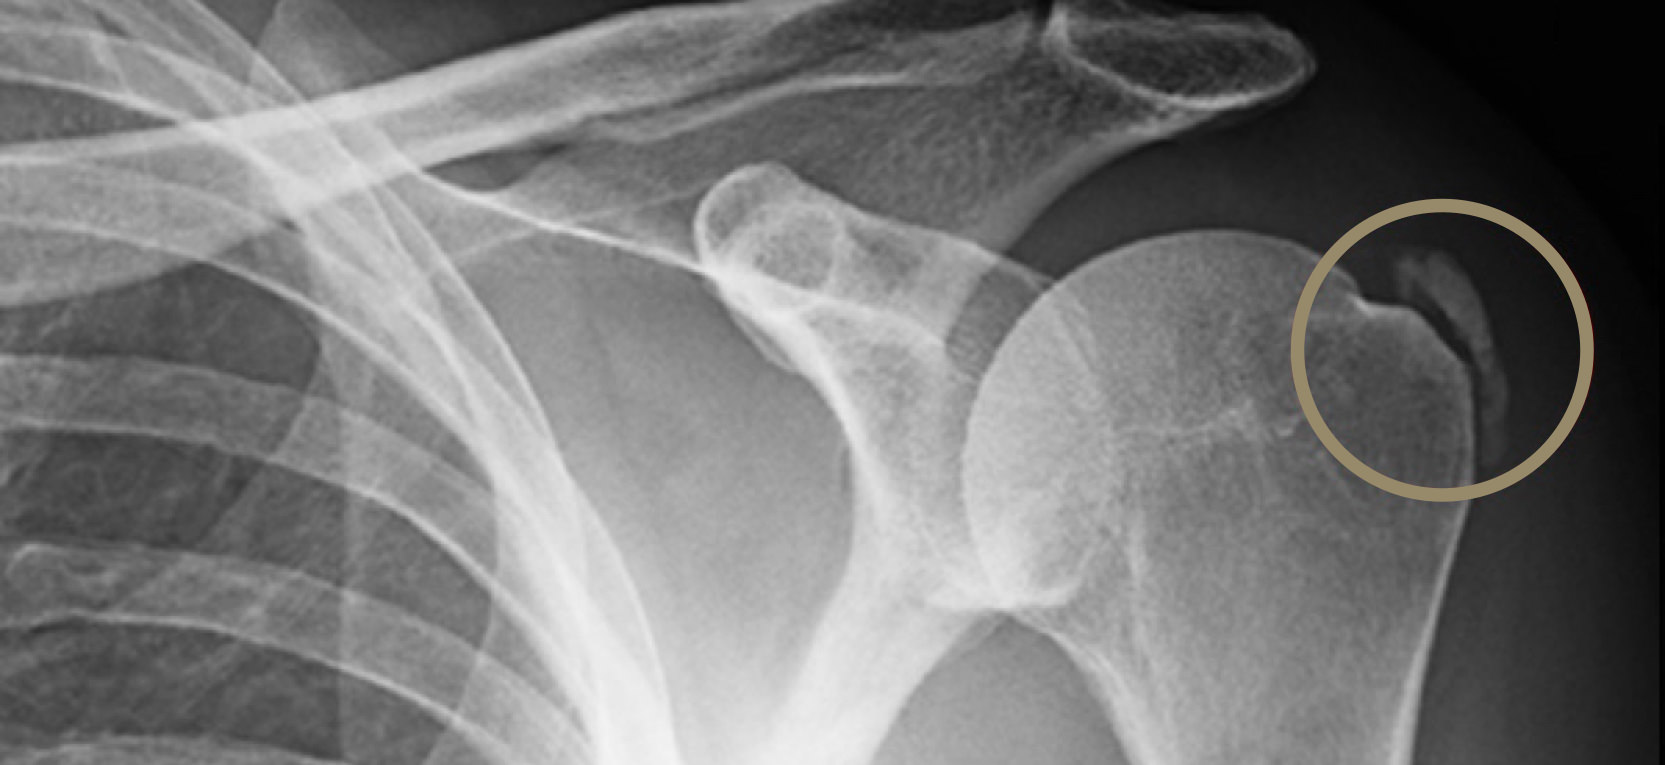

Le couple radiographie/échographie dans les tendinopathies calcifiantes de l’épaule Figure 3

Résumé. La tendinopathie calcifiante de l’épaule est une affection fréquente dont les modalités du traitement restent débattues. Les auteurs de ce symposium ont revu rétrospectivement 450 patients opérés sous arthroscopies pour une tendinopathie calcifiante de l’épaule, avec une imagerie systématique de la coiffe des rotateurs.. Si la calcification a une seule définition, elle a plusieurs étiologies, selon l’endroit où elle se matérialise. De l’épaule aux artères coronaires en passant par les seins et la prostate, tour d’horizon des causes et des traitements de ces dépôts plus ou moins douloureux et graves. Sommaire.